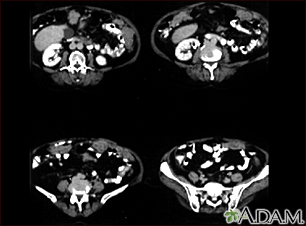

TC de la parte inferior del abdomen que muestra una metástasis del cáncer de los ovarios hacia el peritoneo.